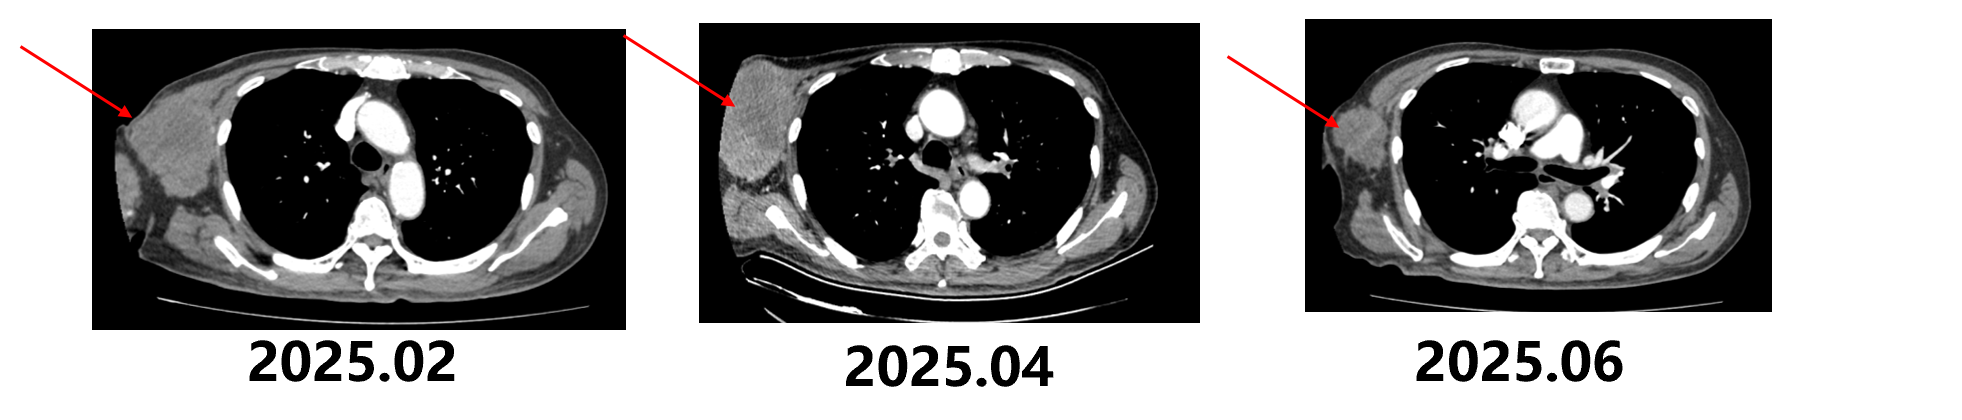

2025.1患者入组“一项评估IB-T101治疗晚期透明细胞肾细胞癌的安全性和有效性的开放、单中心研究”CD70 CAR-T临床试验:患者2025.1.15完成单采,2.22完成细胞回输。回输当天发热1日,中性粒细胞计数降低 CTCAE分级1级。

2025.4 CT示:右侧腋窝肿块,考虑转移,较前(2025-2-12)增大; 右侧腋窝及锁骨上窝淋巴结增多、增大,考虑转移,锁骨上淋巴结较前缩小。研究出组后,加用特瑞普利单抗治疗,伤口护理。